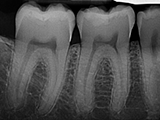

| X-Ray Example |

X-ray taken with the Pro Sensor |

Dental X-Ray Comparison

DentiMax

X-ray taken with the DentiMax sensorOpen Sensor